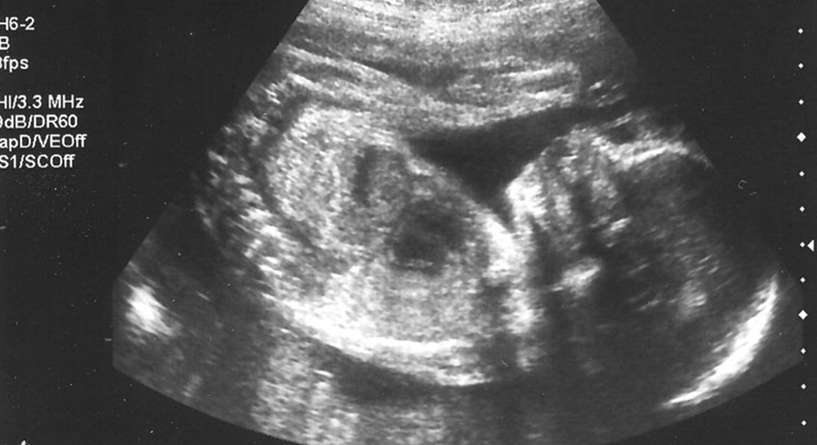

في الواقع، ان السونار هو جهاز يعمل بالموجات ما فوق الصوتية التي يرسلها على شكل ترددات عالية عبر الرحم وتنعكس على شاشة تظهر حركات الجنين ووضعيته في الرحم. وتظهر هذه الصور باللونين الاسود والابيض وتعكس نمو الجنين. ولذلك، فان السونار هو من اهم الاجهزة في الحمل لانه يواكب حركة نمو الجنين ويقدم لمحة شاملة عن كيفية نموه شهرا تلو الآخر.

كثيرا ما تتساءل الحاملكيف اعرف جنس الجنين واذا كان بالامكان تحديد شكل الجنين الذكر والانثى بالسونار. في الواقع، تبين انه يمكن معرفة جنس الجنين في رحم المراة من خلال السونار الا اذا كان الجنين في وضعية خاطئة.

ويمكن تحديد جنس الجنين بالسونار في الشهر الثالث من الحمل اذا كان الجهاز متطوراً، لكن تكون النتائج اوضح في الشهر الخامس منه حيث تكون قد اكتملت الاعضاء الجنسية وبرزت بشكل واضح.

اما في ما يتعلق شكل الجنين الذكر والانثى بالسونار، فيؤكد الاطباء انه اذا كان الجنين انثى تظهر 3 خطوط بيضاء على الشاشة وهي عبارة عن فتحة الفرج والشفرين اللذين ينموان لاحقاً بعد البلوغ ليغطيا الفتحة. اما اذا كان الجنين ذكر، يظهر العضو الذكري اي القضيب بوضوح، او تظهر كرتان على الشاشة تمثلان الخصيتين.

اذا، كما سبق وكشفنا لك يساعد السونار على تحديد جنس الجنين ويمكن ان يبان شكل الجنين الذكر والانثى بالسونار وانما في الشهر الثالث او الرابع من الحمل واذا كان الطفل قد اتخذ الوضعية المناسبة. وبالتالي فان السونار اكثر دقة من طرق كشف جنس الجنين الاخرى التقليدية.